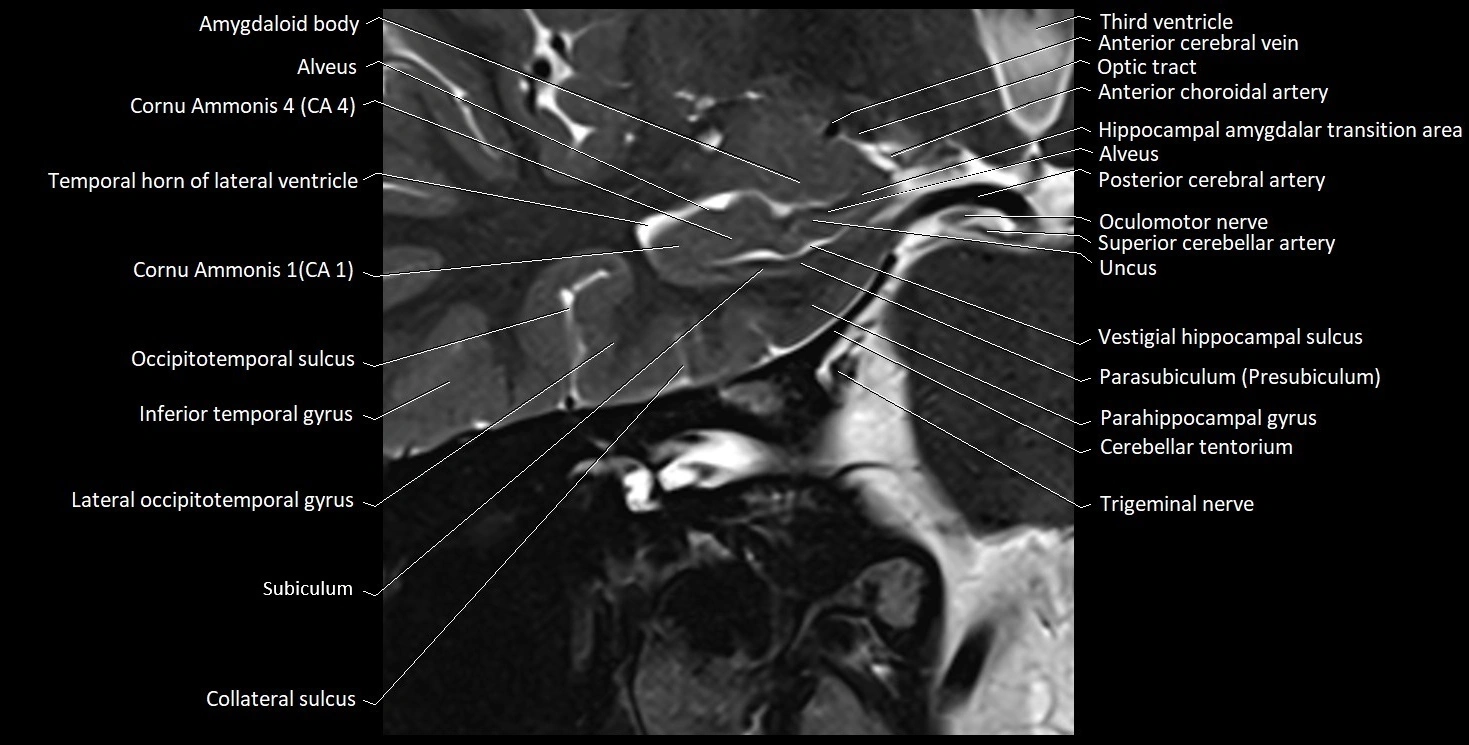

The alveus of the hippocampus is a thin, white matter layer covering the superior (ventricular) surface of the hippocampus within the temporal horn of the lateral ventricle. It consists of myelinated efferent fibers arising primarily from the pyramidal neurons of the hippocampus. These fibers converge medially to form the fimbria of the hippocampus, which continues posteriorly into the fornix, forming a crucial part of the Papez circuit involved in memory consolidation and emotional processing.

The alveus serves as the initial output pathway of the hippocampal formation, linking it to other limbic structures including the hypothalamus, mammillary bodies, and cingulate gyrus. Because of its intimate relationship with the hippocampal head and tail, it is often evaluated in cases of temporal lobe epilepsy, hippocampal sclerosis, and neurodegenerative diseases.

Location and Structure

• Position: Lies on the ventricular (superior) surface of the hippocampus, beneath the ependyma of the inferior horn of the lateral ventricle.

• Composition: A thin sheet of myelinated axons derived mainly from hippocampal pyramidal cells.

• Course: Fibers run medially along the hippocampal surface to form the fimbria of the hippocampus, which curves upward and backward into the fornix.

• Relations:

• Superiorly: Ependyma and CSF of the temporal horn of the lateral ventricle

• Inferiorly: Pyramidal cell layer of the hippocampus (CA1 region)

• Medially: Fimbria and fornix

• Laterally: Temporal lobe white matter and parahippocampal gyrus

MRI Appearance

T1-weighted images:

• Alveus: Thin linear high signal band (due to myelinated fibers) overlying the hippocampal gray matter.

• Hippocampal gray matter: Intermediate signal intensity.

• CSF of lateral ventricle: Dark (low signal).

T2-weighted images:

• Alveus: Low signal line overlying brighter hippocampal gray matter.

• CSF: Bright hyperintense.

MRI images

image